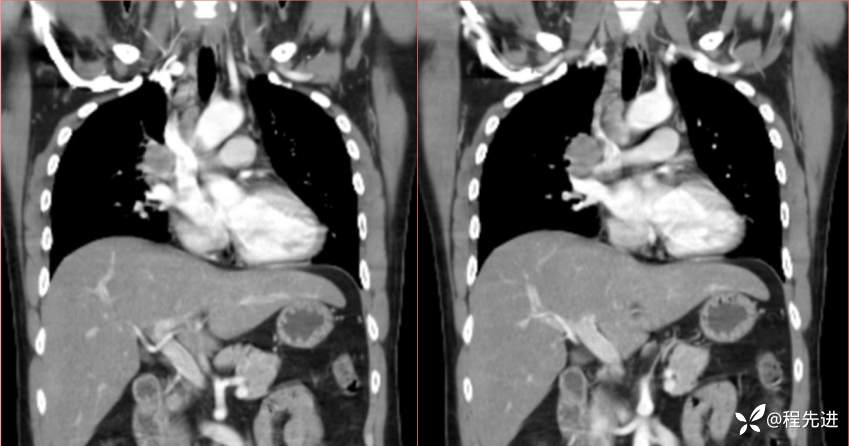

2023国庆特别精彩病例(一)|阵发性刺激性咳嗽,咳少量白色粘液痰1周|结果已公布

患者年龄:34岁

简要病史:患者一周前无明显诱因出现阵发性刺激性咳嗽,咳少量白色粘液痰,咳嗽无明显昼夜节律性,无发热、畏冷、寒战,无头痛、胸闷、胸痛,自行服药后 (具体不详) 症状无缓解,3天前外院胸片检查示右上病变

辅助检查:肺肿瘤标志物:神经元特异性烯醇化酶(NSE):35.72ng/ml(参考值0-16.3);非小细胞肺癌相关抗原211、胚抗原糖类抗原125、铁蛋白、鳞状细胞癌抗原未见异常